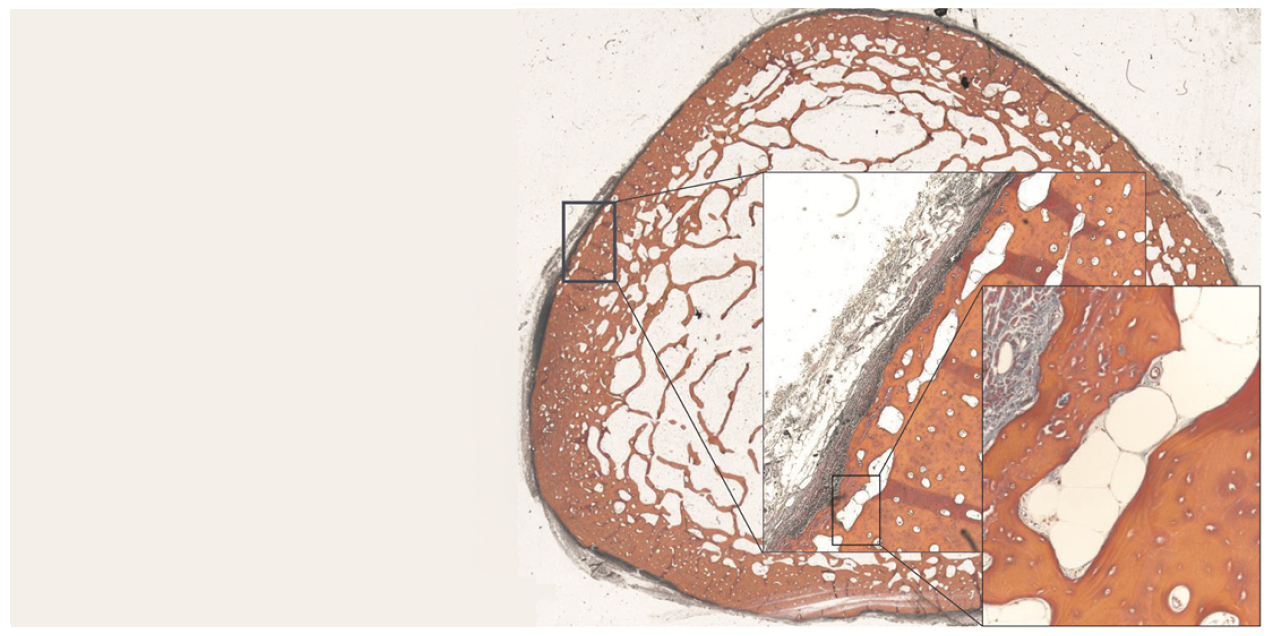

This research introduces a new imaging analysis method to measure how cortical bone pores cluster, connect, and realign, improving understanding of how pore structure contributes to…

This research evaluates how well standard micro CT can measure bone tissue mineral density and composition by comparing it to synchrotron micro CT, with the goal of improving…

This research shows that constant Gs signaling in osteoblasts causes abnormal bone formation, producing immature, poorly mineralized bone in a mouse model of fibrous dysplasia.